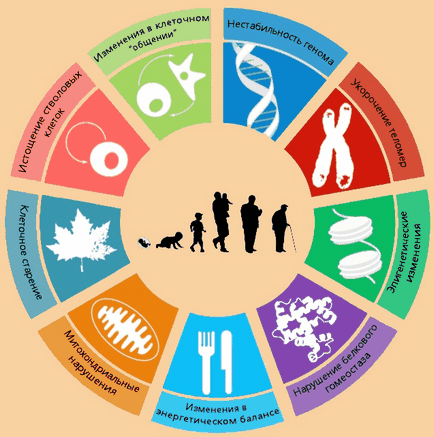

Людина помирає від того, що старіють клітини тіла.

Малюнок 2. Молекулярні ознаки старіння

Клітини мозку не старіють так виражено, як клітини тіла. Мозок вмирає в основному через проблеми з кровоносними судинами, що живлять його, а судини гинуть через те, що клітини до старості втрачають здатність ефективно відновлюватися.

7 основних типів пошкоджень організму:

- Загибель і атрофія клітин

- Пошкодження ядерної ДНК

- Пошкодження мітохондріальної ДНК

- Накопичення внутрішньоклітинного сміття

- Накопичення позаклітинного сміття

- Позаклітинні з'єднання, зшивання

- Поява безсмертних (ракових) клітин